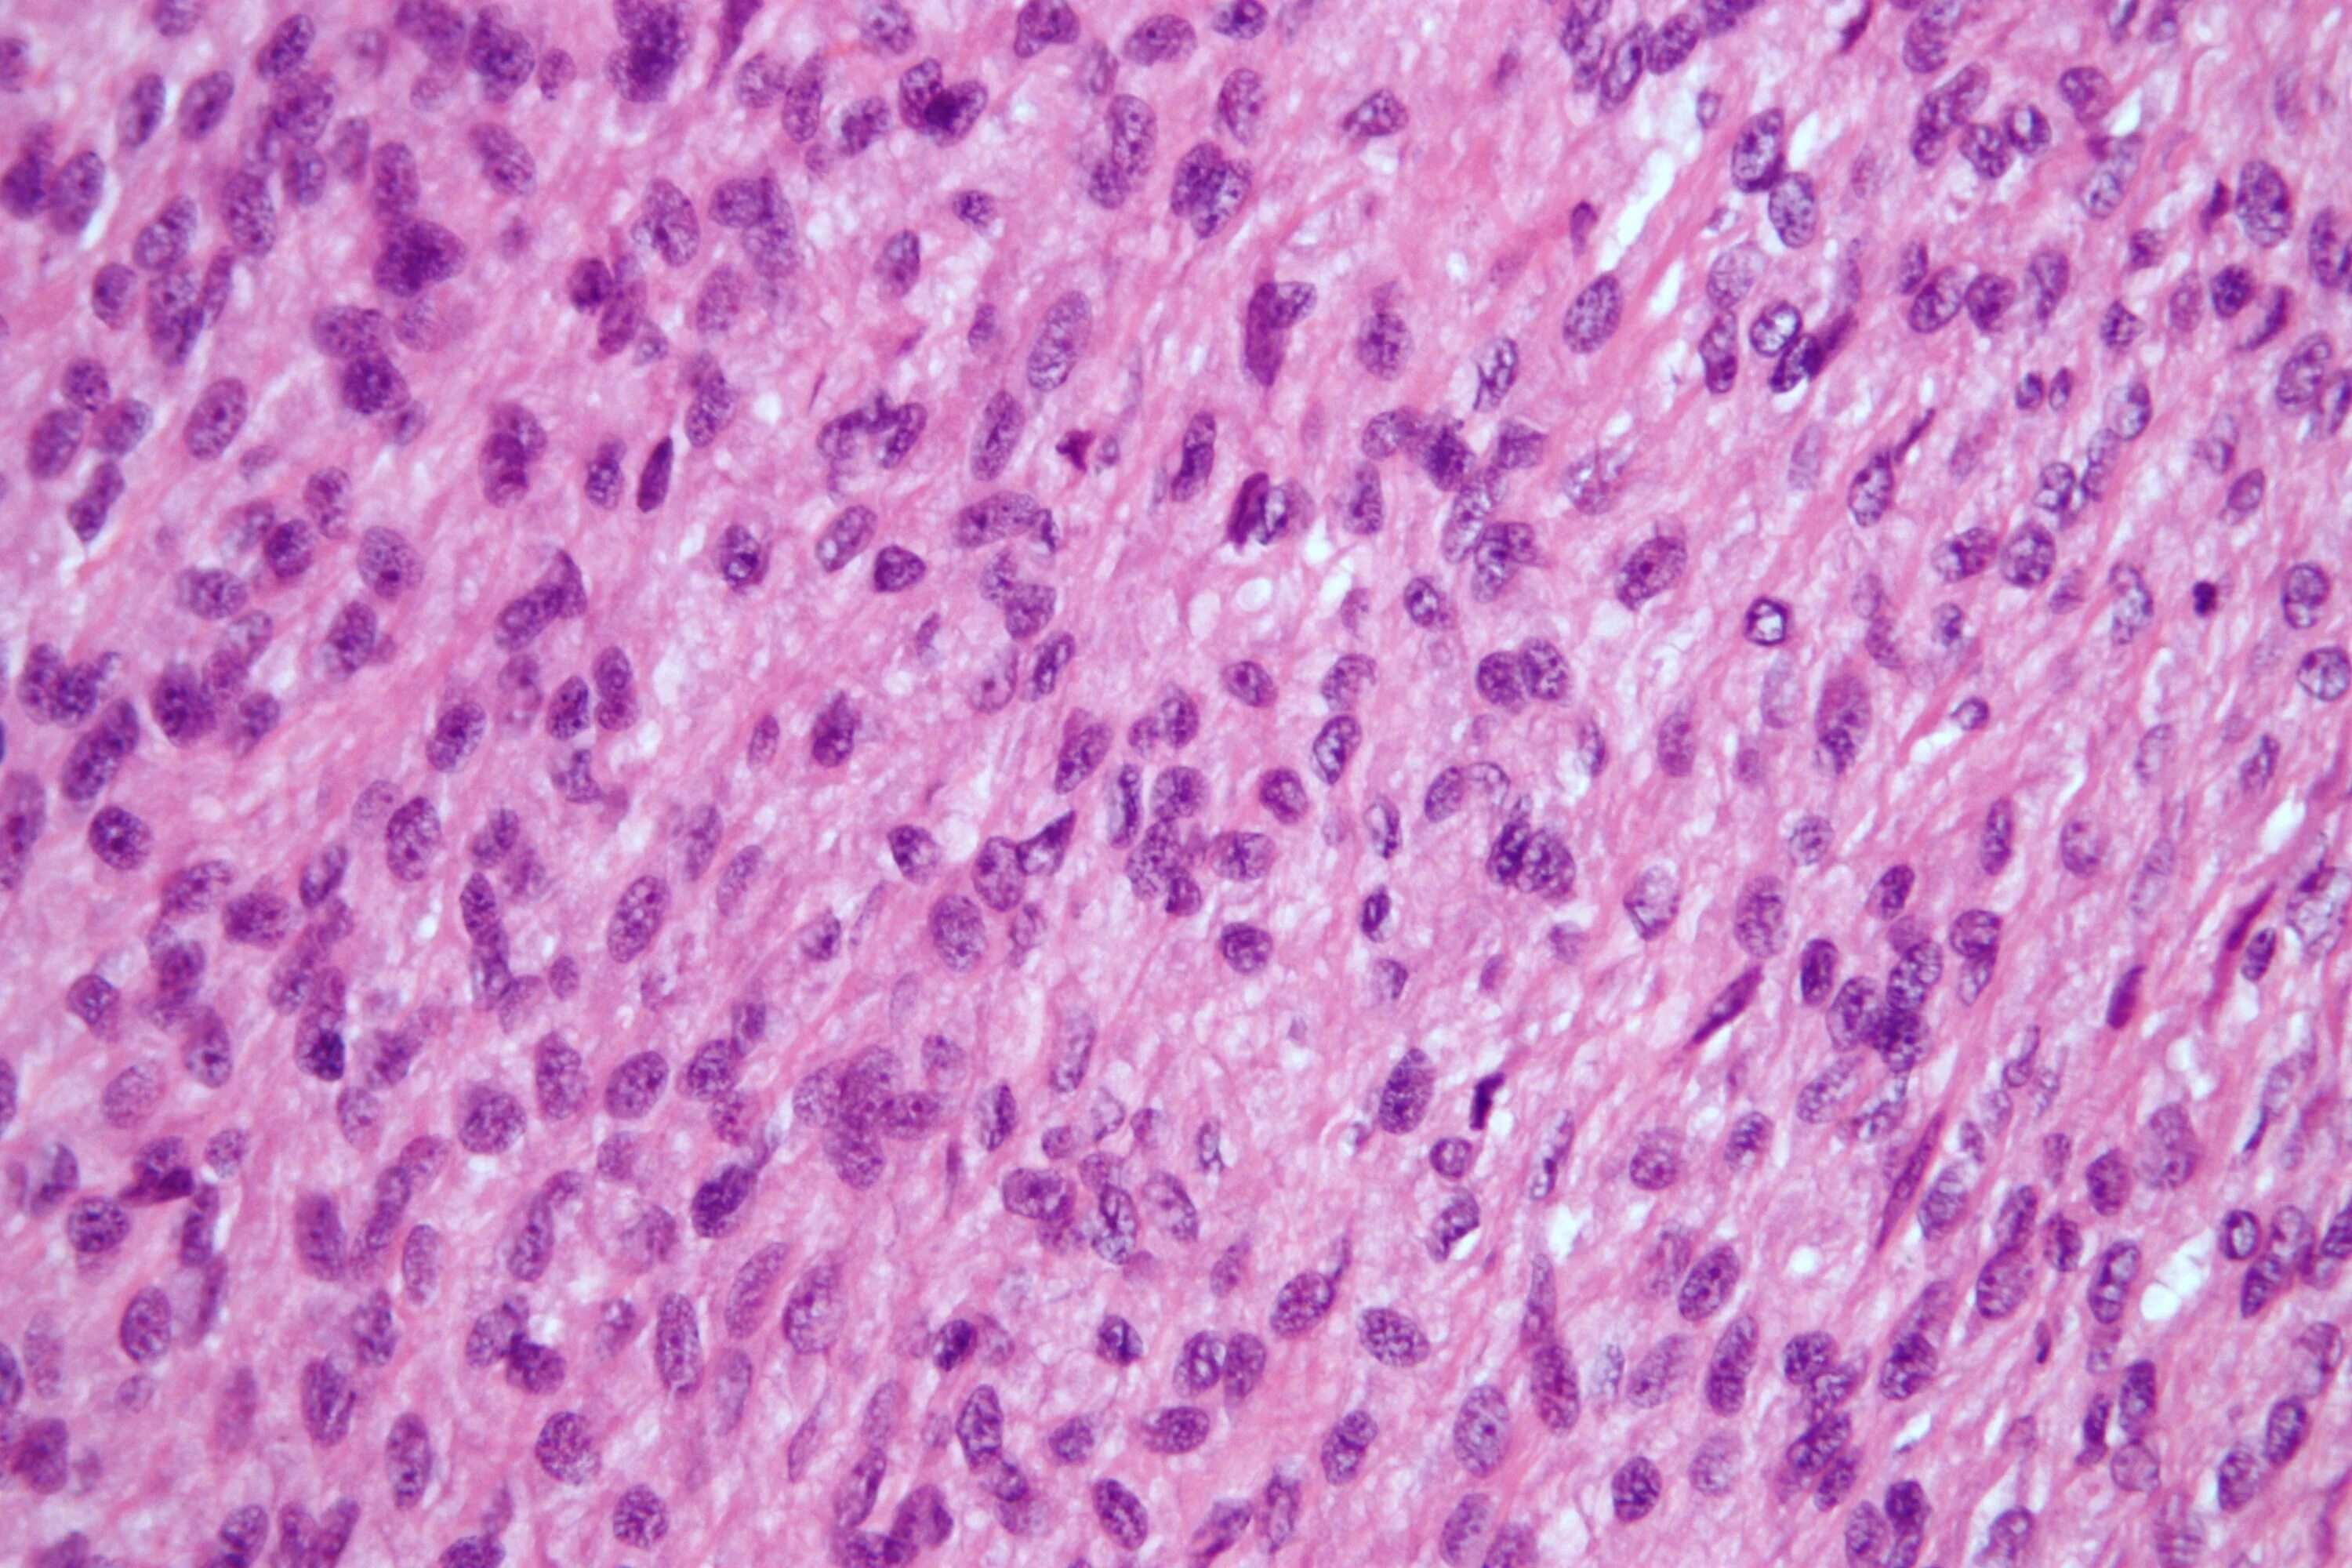

Гистология фото